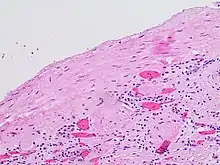

Category III

- Indeterminate cystic masses with thickened, irregular or smooth walls or septa with measurable enhancement. Approximately 40 to 60% of these lesions are ultimately found to be malignant, most commonly in the forms of cystic renal cell carcinoma and its multiloculated variant.[8][9][10] The remaining lesions are benign and include hemorrhagic cysts, chronic infected cysts, and multiloculated cystic nephromas.